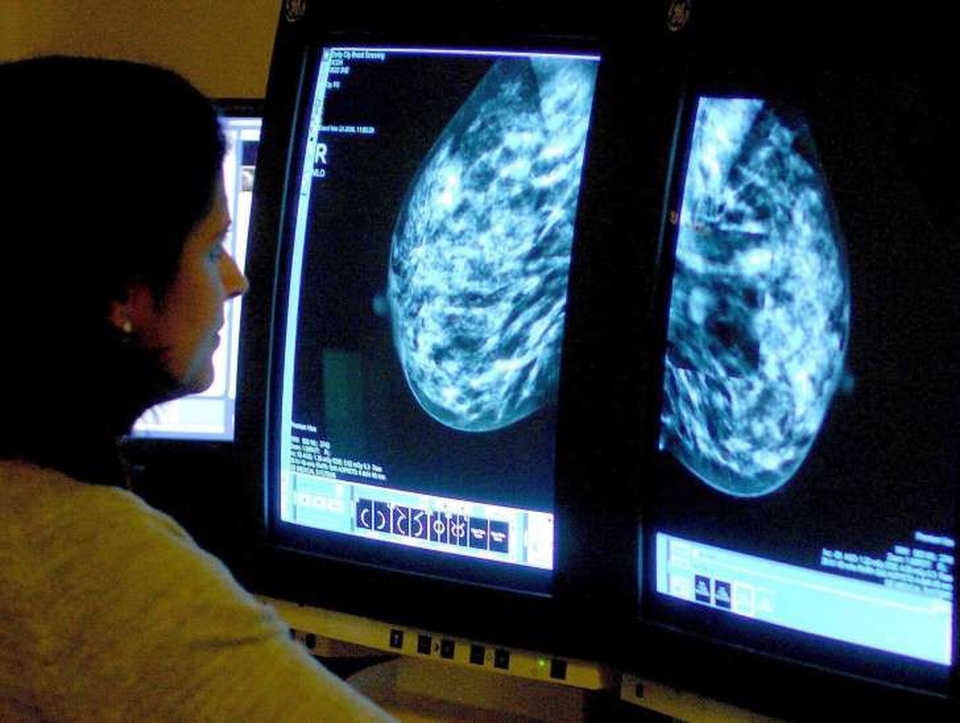

Ung thư vú có thể quay trở lại sau 20 năm

(Dân trí) - Theo các nhà nghiên cứu, ung thư vú có thể “âm ỉ” và tái phát sau 20 năm trừ khi bệnh nhân duy trì uống thuốc để ngan chặn nó.